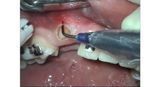

- Chirurgia mucogengivale

- Gengivectomia-gengivoplastica

- Endodonzia

- Parodontologia